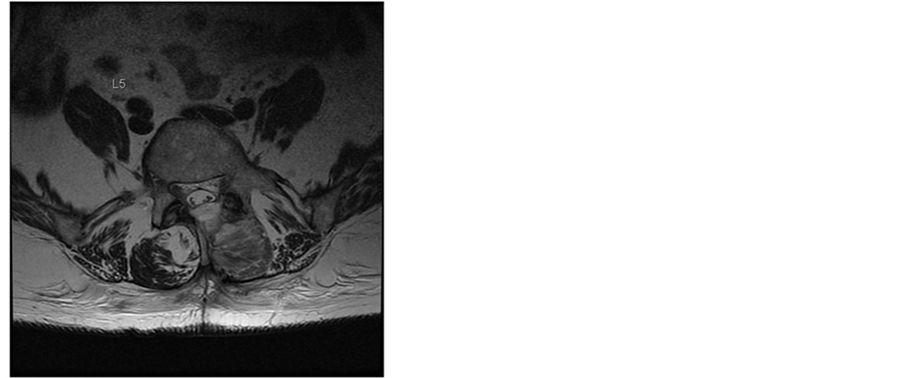

In the next weeks our patient recovered slowly. MRIs were performed and showed a slow reabsorption of the haematoma (Figure 2 and Figure 3). Clinically at the 3-month control the patient had no neurological signs or symptoms (such as radicular pain, neuropathic pain or paresthesia) and no signs of polyradiculo(neuro)pathy.

Figure 3. T2-weighted MR images of the lumbar spine in sagittal and transaxial planes 3 weeks after surgery. The hematoma has completely resolved. Patients consent obtained.